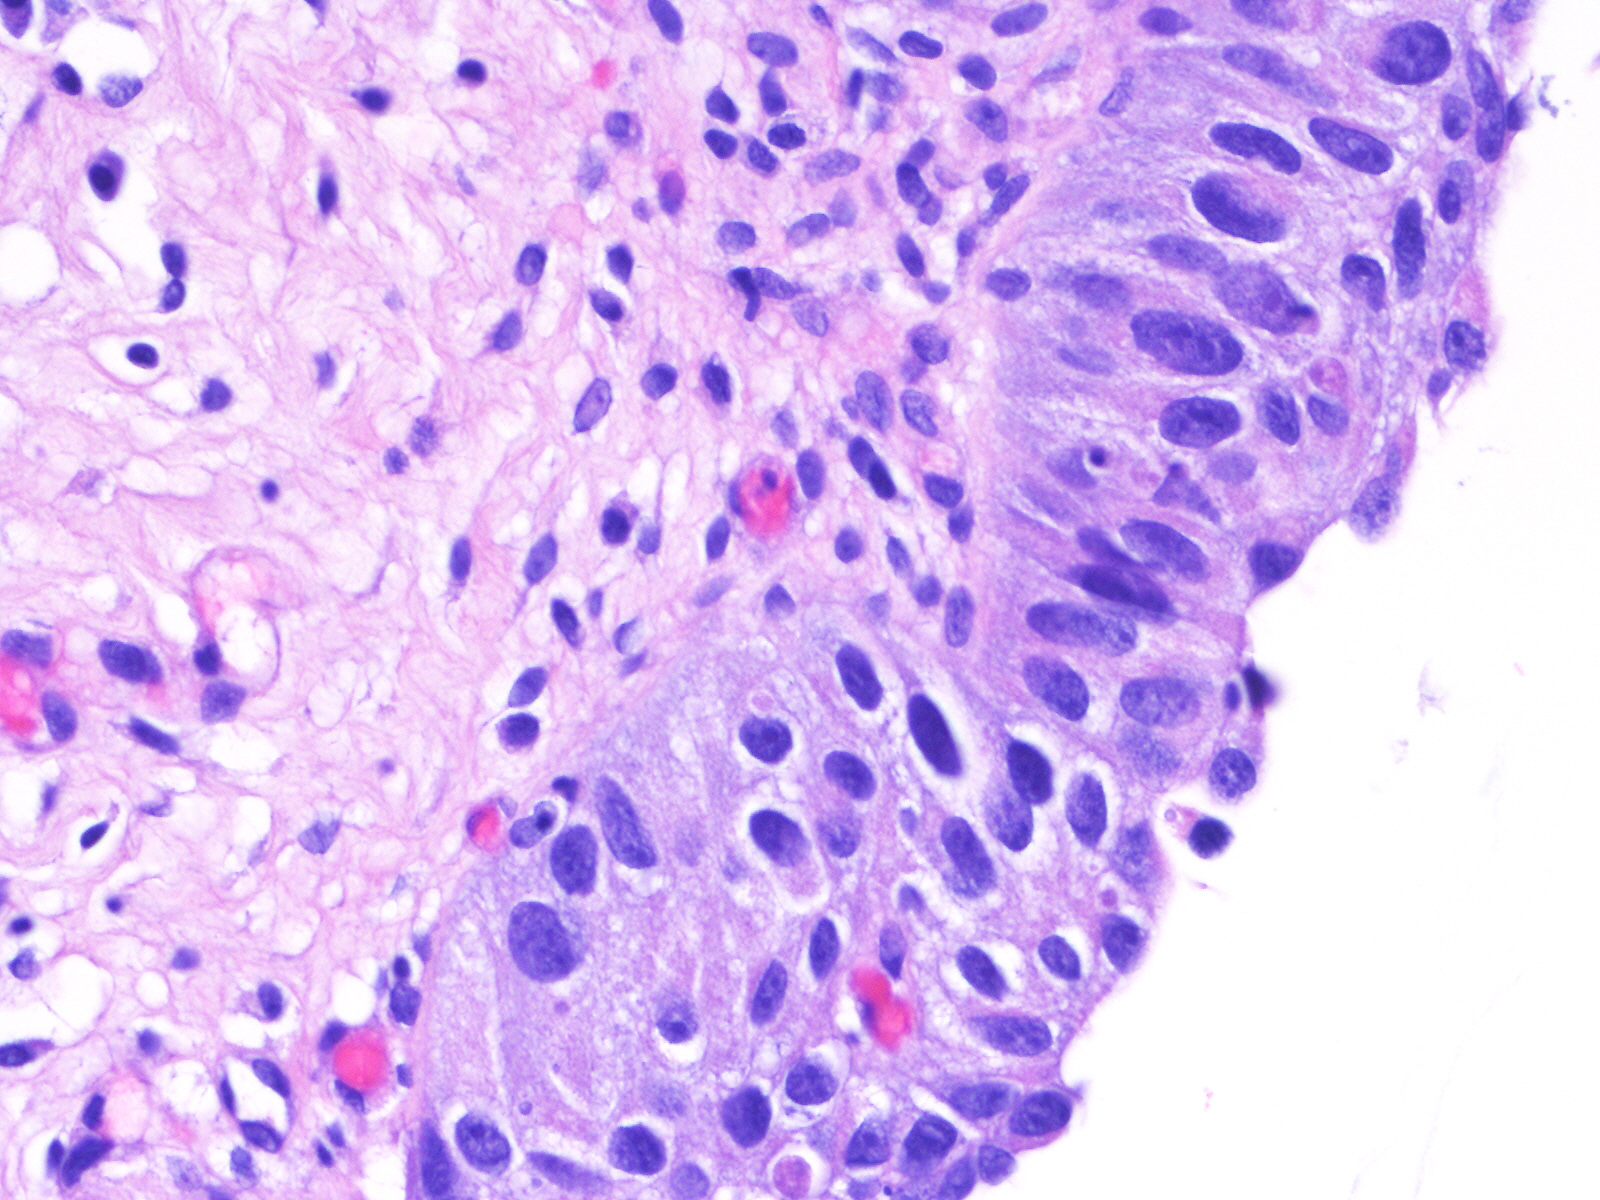

Consensus grade: Carcinoma in situ (CIS)

A 60-year-old man had atypical urothelial cells on urine cytology. Cystoscopy revealed several lesions in the bladder that were biopsied. He had a history of bladder urothelial CIS treated with intravesical BCG therapy and 3-month follow-up cystoscopies and cytologies were unremarkable.